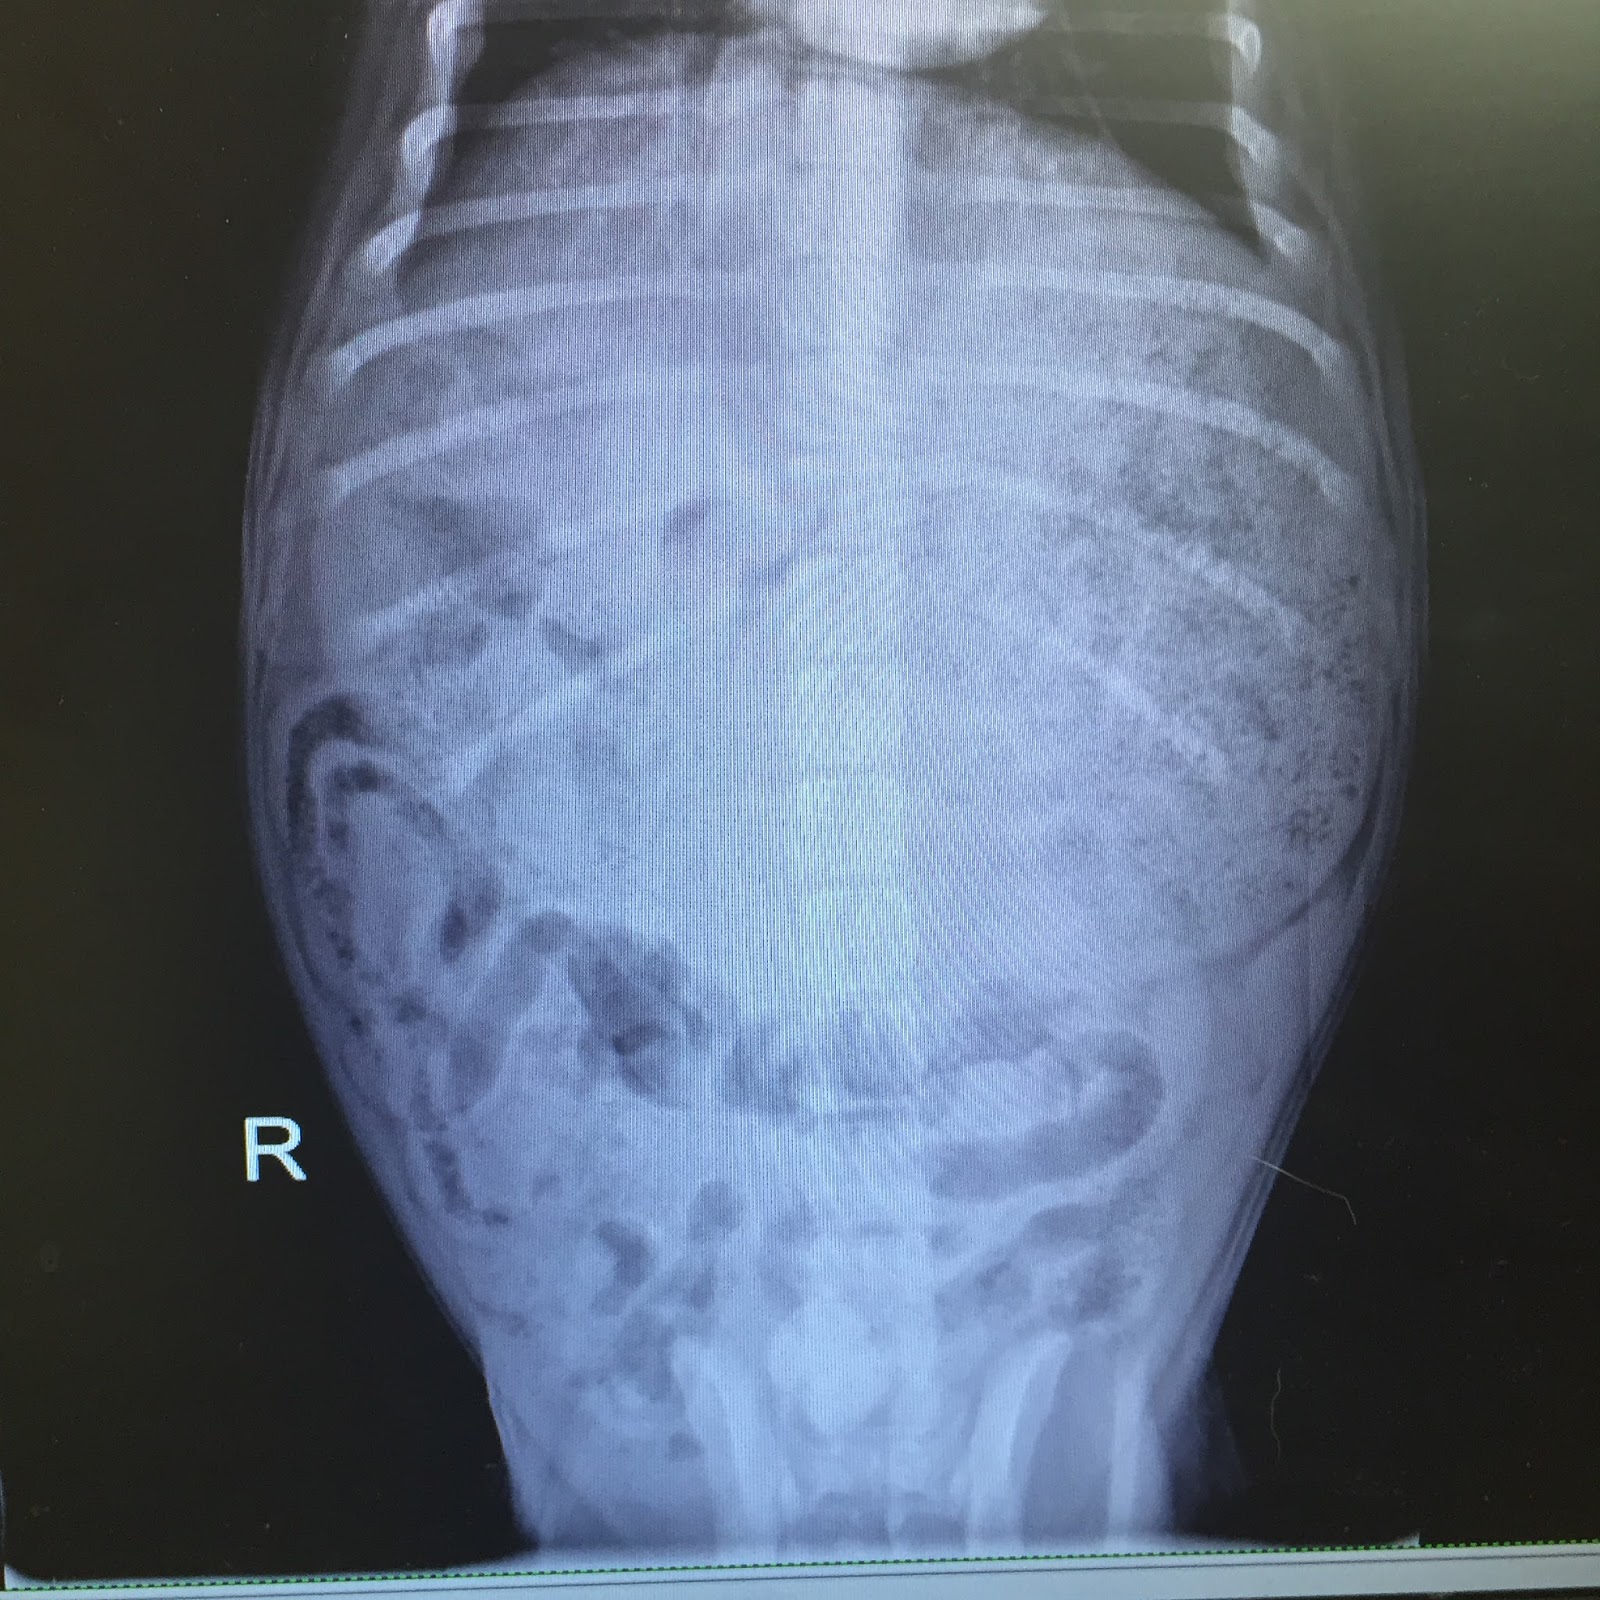

When the vet ushered us back to a room, Bill’s x-rays were up on the screen and I immediately felt sick to my stomach.

| The top portion of the x-ray that sort of resembles a circle should be the size of a clementine. This is Bill’s stomach. Our vet told us it was, in fact, the size of a cantaloupe. |

Yowza. Thankfully, we had him to the vet in time. No torsion. No immediate health threat. BUT! How did this happen? What is the cause?